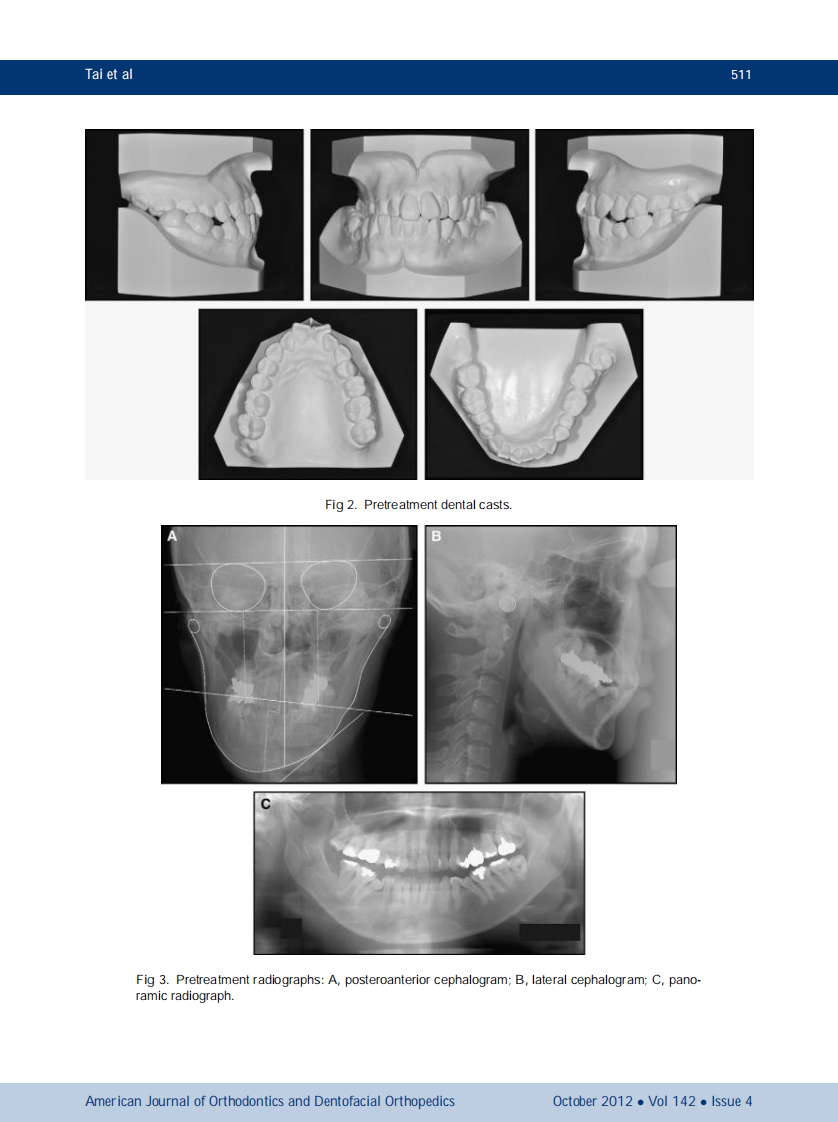

AJO-DO

1-s2.0-S0889540612006312-main.pdf